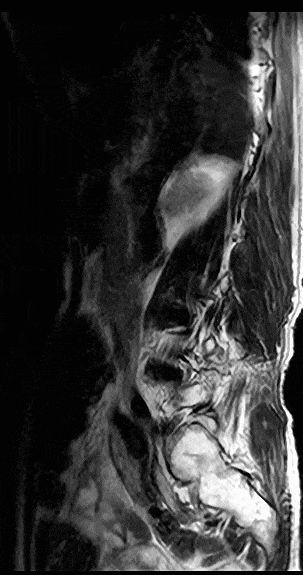

对分辨率的追求驱动着CT技术的进一步发展。一方面是聚焦硬件的探测器革新,例如0.25mm的超薄探测器切割、光子计数探测器等;另一方面,则是通过图像重建算法的辅助来实现,例如从传统的FBP到迭代算法、再到如今的深度学习重建算法。而佳能医疗将AI图像技术与宽体探测器深度融合,将CT图像分辨率提升至了新高度。

基于佳能医疗的深度学习神经网络平台,结合Aquilion Precision 4K级高清数据采集平台进行训练,得到高清AI引擎PIQE。结合宽体CT平台,PIQE可以同时提升图像分辨率和覆盖宽度,实现任意心率及心律不齐下的高清心脏成像,尤其有利于对心血管支架和斑块的显示。